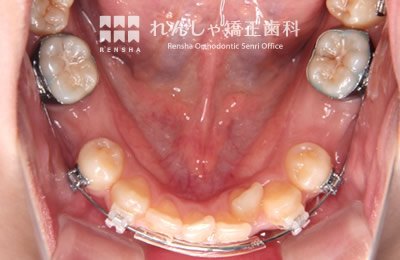

中高生

永久歯列はほぼ完成してしますが、歯列を側方だけでなく後方へも拡大し、埋まっていた右上奥歯を引っ張り出しています。

| 主訴 | 埋まったままでてこない歯がある |

|---|---|

| 診断名 | Angle Class II 小臼歯の埋伏と叢生を伴う上顎前突 |

| 初診時年齢 | 13歳5か月 |

| 装置名 | マルチブラケット装置 |

| 抜歯非抜歯 | 非抜歯 |

| 治療期間 | 2年3か月 |

| 費用の目安 | 約82万円+消費税(検査料金、都度の処置費用等も合わせた総額) |

| リスク副作用 | 歯の移動に伴う軽微な歯根吸収、歯槽骨吸収、歯肉退縮(本症例では軽度の歯根吸収を認めた)、矯正器具装着中のカリエスリスク増大(本症例ではカリエス発生無し) |